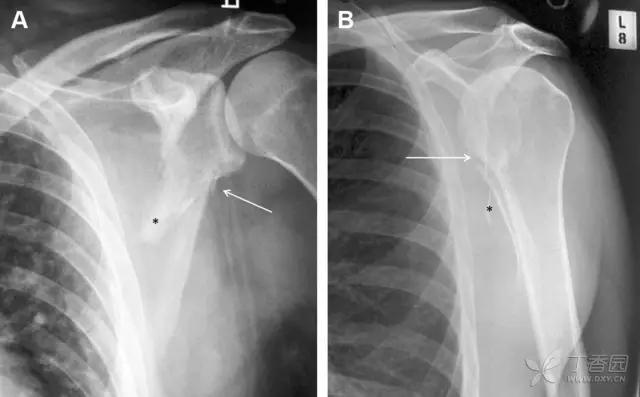

28 骨折伴盂肱关节不稳

肩关节是最容易脱位的关节之一,肩关节脱位常伴随其它结构的损伤,如血管神经损伤、肩袖损伤、盂唇损伤、Bankart 损伤等。脱位本身诊断往往是明确的,容易被忽略的是其继发的伴随损伤。

需要仔细评估肱骨头、大结节、关节盂边缘、肩峰、喙突等结构。典型的 X 线投射角度包括:内旋位前后位片、外旋位前后位片(Grashey 位)、侧位(肩胛骨 Y 位)、腋位片以及改良腋位片。

图 6 肩关节前脱位伴有 Hill–Sachs 和 Bankart 损伤:(A~C)肱骨头后外侧撞击骨折,白色箭头所示为骨折的内侧边界;(A)内旋位前后位片,(B)「V」形压缩骨折的下边界(虚线短箭头),(C)Garth 位(轴向投影)示 Hill–Sachs 损伤(虚线和实线折箭头),特别是对骨性 Bankart 损伤的诊断有帮助。(D、E)MRI 进一步证实了损伤

图 7 肩关节后脱位伴有反 Hill–Sachs 损伤。(A)外旋位前后位片可见一硬化带(黑箭头),此「凹槽征」与肱骨头关节面平行;(B)腋位片进一步证实了骨折的存在